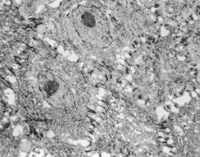

2. 電鏡觀察 受傷當(dāng)日上皮組織變性壞死,可見單核細(xì)胞核偏移、固縮,并有吞噬現(xiàn)象(圖5-3-12)。

5-3-12 燒傷當(dāng)日,單核細(xì)胞核偏移,固縮,并有吞噬現(xiàn)象  TE×8000